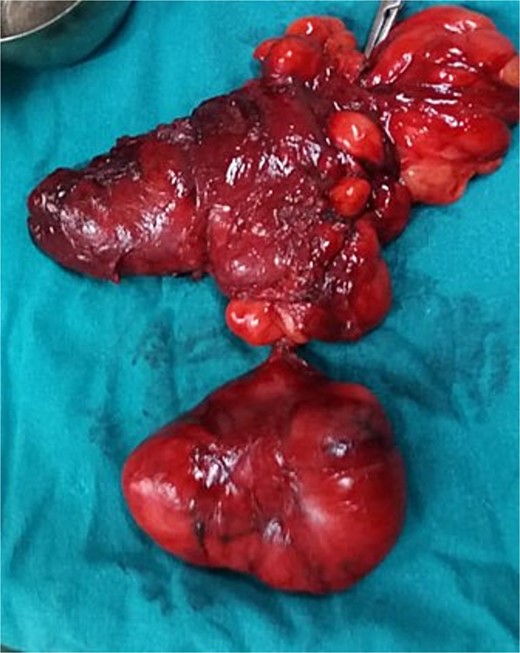

One month after the referral, an excisional surgery was performed. The procedure began with a skin incision through the platysma muscle, followed by dissection beneath the superficial layer of deep cervical fascia (SLDCF) to identify the mass (Fig. 3). Next, we identified the carotid artery after dissecting the inferior pole of the mass from it and proceeded superiorly with great caution (Fig. 4). The mass was completely removed without disturbing its capsule. The mass was observed grossly as an encapsulated, reddish, lobulated mass (Fig. 5). Due to the extensive dissection and the large size of the mass, a drain was placed and then it was removed 2 days after. The patient was subsequently discharged home without any noticed complications. The pathology results were consistent with angiolipoma (Figs 6 and 7). A 1-year follow-up revealed no recurrence.

Gross image of the excised lesion, appearing as a reddish, lobulated mass.